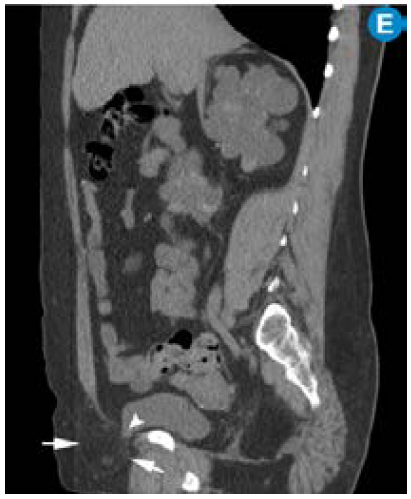

Por su alta sensibilidad, disponibilidad y bajo costo, la ecografía renal es el estudio inicial con el que se pueden observar riñones grandes con quistes bilaterales, múltiples y tamaño variable (figura 1); sin embargo, es altamente dependiente del operador y es menos sensible para detectar quistes <1cm que se visualizan mejor en la escanografía o en la resonancia magnética 24. Pese a que en la actualidad no existen criterios estandarizados en estas dos técnicas imagenológicas para el diagnóstico de la PKD, la tomografía computarizada (TC) y la resonancia magnética (RM) son más sensibles para el diagnóstico de los quistes en los casos dudosos, la detección de complicaciones, la valoración de la progresión y la respuesta al tratamiento 25 (figura 2).

En la ARPKD, el diagnóstico puede ser realizado en el período intrauterino, neonatal o en los primeros meses de vida por medio de una ecografía renal en la que se observan los riñones aumentados de tamaño, con pérdida de la relación corticomedular, hipoplasia pulmonar y oligohidramnios debido al bajo gasto urinario 31. En edades posteriores se prefieren las imágenes por TC y RM para seguimiento o, como ya se mencionó, para casos dudosos. En las fases tempranas, los riñones pueden ser de tamaño y forma normal; en las fases posteriores aumenta el número y el tamaño de los quistes, con distribución difusa del parénquima, aumento del tamaño (se alcanzan longitudes de hasta 40cm) y, por consiguiente, aumento del volumen renal. La RM es la técnica de elección empleada para la volumetría de los quistes y del parénquima como indicadores de progresión o de respuesta al tratamiento.